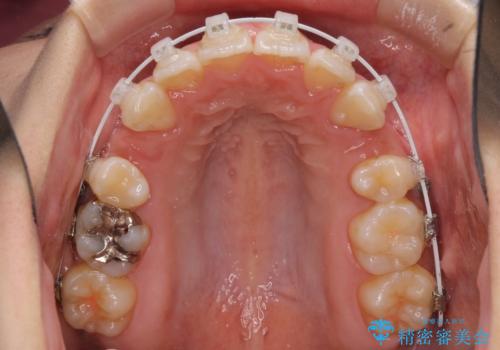

- 審美装置

- 2年5ヶ月

- 10-30回

下顎の正中を上顎に合わせる処置が難航し、期間が長引きました。

最終的には上下の正中も合い、横顔の印象が変わるほどスッキリとした口元となりました。